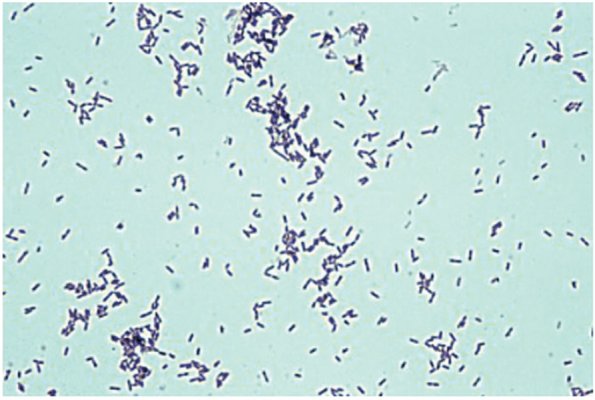

Листерии и листериоз симптомы

Листерии и листериоз симптомы 109 фото